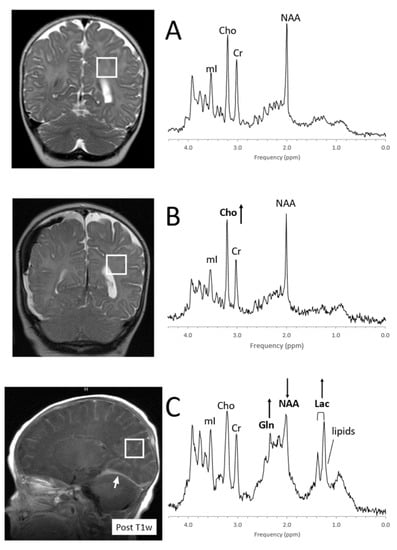

| Lactate (Lac) | Endpoint of anaerobic glycolysis, in normal brain present in cerebrospinal fluid at higher concentrations than in tissue | Disease correlate unknown | Inborn errors of energy metabolism, hypoxic/ischemic injury; tumors, cystic lesions, normal newborn |

| Lipids (Lip) with contributions from macromolecules (MM) | Indicators for cell membrane breakdown when elevated | Disease correlate unknown | Injury/cell death and tumor subgroups |